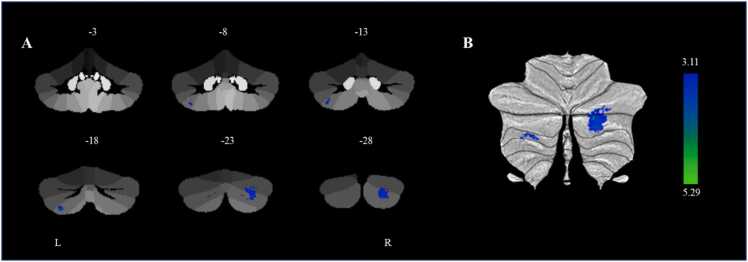

Additionally, we conducted a whole-cerebellum exploratory analysis and found that smaller gray matter volumes in the right cerebellar lobule Crus II (cluster 1) (β = −0.223, p < 0.001, 95% CI [−0.337, −0.109]) and left cerebellar lobule VIIb (cluster 2) (β = −0.262, p < 0.001, 95% CI [−0.392, −0.132]) at baseline were associated with a higher p factor at baseline controlling for gender, age, site, parental education level, and TIV (Table 2 and Fig. 2). We further found that smaller gray matter volume in the left cerebellar lobule VIIb at baseline was associated with higher p factor at follow-up after controlling for the autoregressive p factor (β = −0.211, p < 0.005, 95% CI [−0.343, −0.054]). However, the gray matter volume in the right cerebellar lobule Crus II at baseline was not significantly associated with the p factor at follow-up. Therefore, further mediation analysis was not performed for the gray matter volume in the right cerebellar lobule Crus II. Further analysis showed that age (t = −0.574, p = 0.566), gender (t = 0.235, p = 0.814), site (t = 0.662, p = 0.508), and parental education level (t = −1.373, p = 0.171) did not significantly moderate the longitudinal prediction of the baseline left cerebellar lobule VIIb on the follow-up p factor. These results aligned with the findings from the ROI analysis. We also conducted a linear mixed model analysis, which yielded similar results to the present findings. For more detailed information, please see the results section of the Supplemental Material.

Table 2: Differences in cerebellar gray matter volume and with p factor from cerebellar voxel-based morphometry.

| Cluster size (k) | Peak Region | MNI Coordinates | T-score | R2 (p factor) | ||

|---|---|---|---|---|---|---|

| x | y | z | ||||

| 973 | The Right Cerebellar Lobule Crus II | 27 | -83 | -36 | 5.29 | 0.031 |

| 183 | The Left Cerebellar Lobule VIIb | -31 | -70 | -55 | 4.31 | 0.033 |

Note.n = 473; MNI, Montreal Neurological Institute.